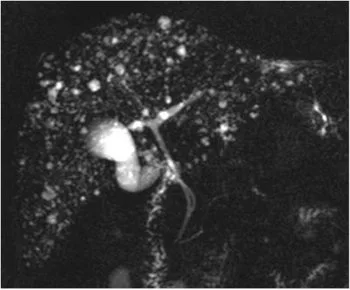

Figure 18. Mise en évidence d’une formation polypoïde (A, têtes de flèche) dans la lumière du canal hépatique commun. Cette coupe de bili-IRM montre les rapports entre le pôle supérieur de la lésion et la convergence biliaire supérieure. On note par ailleurs un abouchement variant sur le canal hépatique gauche du canal sectoriel postérieur droit (flèche). L’hypersignal tissulaire en T2 de la lésion (B) et son rehaussement en T1 après injection de gadolinium (C) montrent qu’il s’agit d’une tumeur et non d’un simple calcul ou d’un conglomérat de sludge. L’analyse de la pièce de résection chirurgicale a retrouvé un adénome tubulo-villeux de 2,5 cm de grand axe, dégénéré sous la forme d’un adénocarcinome bien différencié de type biliaire